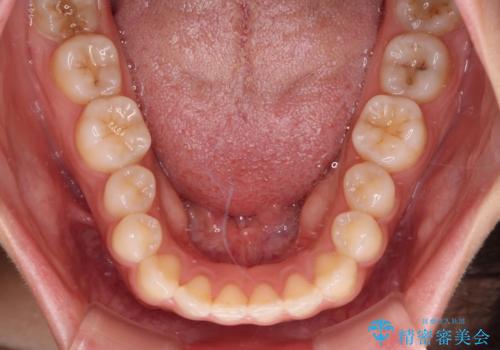

- 上顎前歯の叢生を気にして来院された患者様です。

下顎前歯や上下奥歯の咬み合わせには殆ど問題がないため、上顎前歯のみを矯正する治療を提案しました。

ワイヤー装置でもインビザラインでも可能でしたが、前歯のみをきれいに排列するのであればインビザラインの方が仕上がりが良いので、インビザライン・ライトにて治療を行うこととしました。